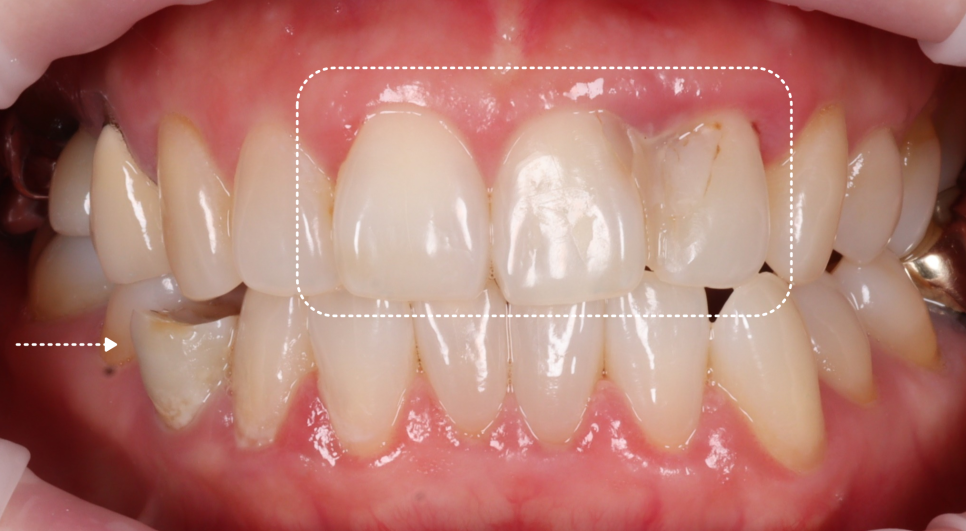

이번에 내원하신 환자분은 50대 여성으로, 불과 12일 전에 다른 치과에서 앞니 레진 치료를 받으셨다고 해요.

그런데 거울을 볼 때마다 색상이 너무 이질적이고 뭔가 내 치아 같지 않고 치료한 티가 나서 도저히 웃을 수가 없다는 고민으로 찾아오셨죠.

하지만 정밀 검진을 통해 발견한 진짜 문제는 단순히 심미적인 부분만이 아니었습니다.

촬영일 : 251230

앞니 사이 공간을 레진으로

꽉 메워둔 상태였어요.

치아 사이는 반드시 치실이 매끄럽게 통과할 수 있는 미세한 틈이 있어야 음식물 찌꺼기가 빠지고 잇몸이 건강하게 유지돼요.

그런데 이걸 꽉 막아버리니 그 안에서 세균이 번식하며 이미 뼈(치조골)가 흡수되는 치주염이 진행되고 있었죠.

엑스레이에서 현재 환자분 뼈 상태를 그려봤는데요.

앞니 쪽에서 뼈 흡수가 많이 되어 라인이 위로 올라가는 것을 볼 수 있었고, 만져봤을 때 경미한 흔들림도 있었죠..

환자분께 현재 상태의 심각성을 말씀드렸어요.

"지금은 색이랑 형태보다 잇몸 뼈가 흡수되는 게 더 문제입니다. 레진이 분리가 되어서 사이가 닦여야 하는데 붙어있어 관리가 되지 않는 형태예요."라고요.

그동안 잇몸이 부었다 가라앉았고, 피가 났다고 말씀해 주셨어요.